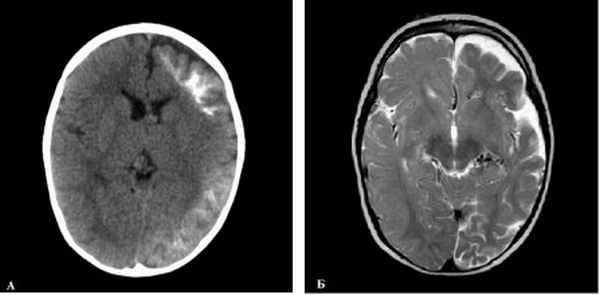

Рис. 1. Нейрорадиологическое исследование головного мозга 20-месячного ребенка с синдромом Стерджа -Вебера: А — КТ (без контрастирования): показана односторонняя кальцификация субкортикального белого вещества левого полушария; Б — МРТ, Т2-взвешеннное изображение: показана субатрофия левого полушария, связанная с локальными аномалиями развития артериальных и венозных сосудов, выявлена аномалия венозного дренажа в обоих полушариях, больше слева, извитые и расширенные вены хориоидеи слева, крупные вены на поверхности правой височной доли вдоль латеральной борозды до правого поперечного синуса. Поражение глаз при СШВ отмечается в 30–60 % случаев в виде ангиоматоза конъюнктивы, сосудистой оболочки глаза, глаукомы, что может привести к потере зрения